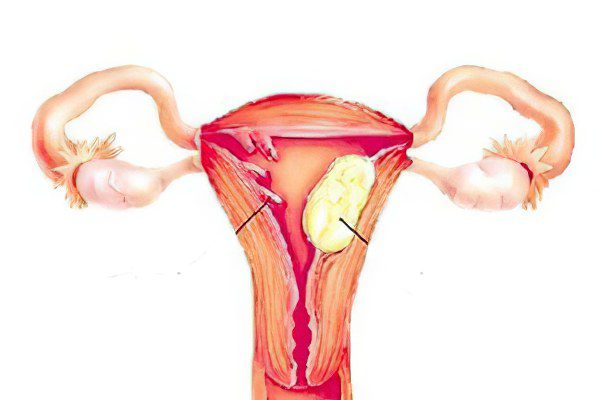

Анатомия женского организма: строение и функции матки

Раздел: Фотопуть к знанию